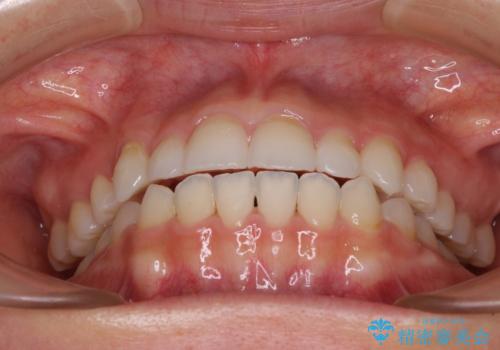

- 前歯のデコボコや八重歯、舌癖による開咬を気にして来院された患者様です。

目立たない装置を希望されたので、上顎が裏側装置のハーフリンガルを選択し、上顎小臼歯1本を抜歯して、補助装置を併用して矯正治療を行うこととしました。

補助装置を事前に使用したことで、あっという間に八重歯が改善し、ハーフリンガルにしては1年半もかからずに治療を終えることができました。